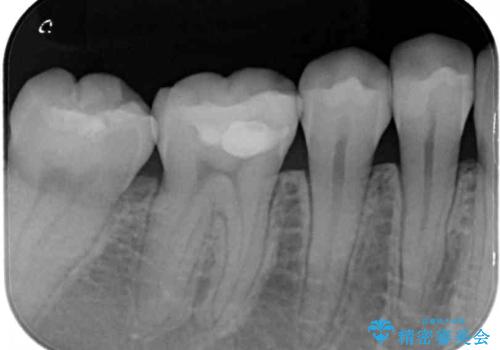

- 下の奥歯(右下7・左下7)にあって目立ってしまう銀歯を白くしたいとのことで来院された患者様です。

セラミックインレーにて修復治療を行うこととしました。

セラミックインレーを装着したことで、とても自然な仕上がりとなりました。